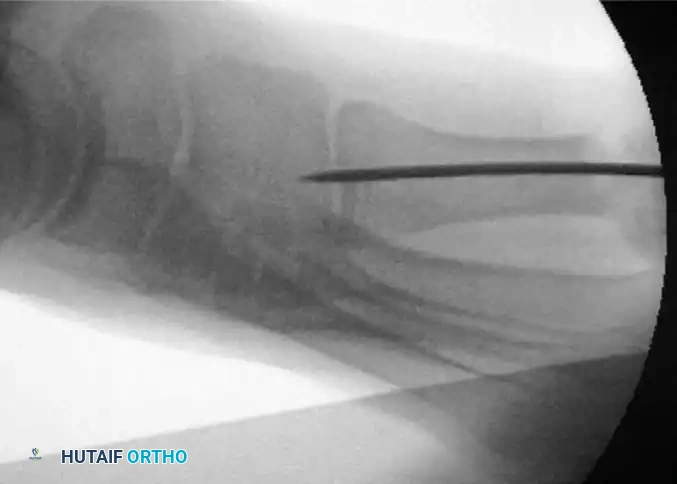

Once the wire is seated proximally, the alignment and hardware placement must be rigorously verified.

- Carefully remove any grooved instruments or tissue protectors used during wire insertion.

- Obtain a true lateral fluoroscopic image to check the trajectory and final position of the K-wire. Ensure the wire has not breached the dorsal or plantar cortices and is firmly seated in the proximal base without causing dorsal elevation of the capital fragment.

FIGURE 81-37 Percutaneous distal metatarsal osteotomy. Lateral fluoroscopic view shows the position of the Kirschner wire.